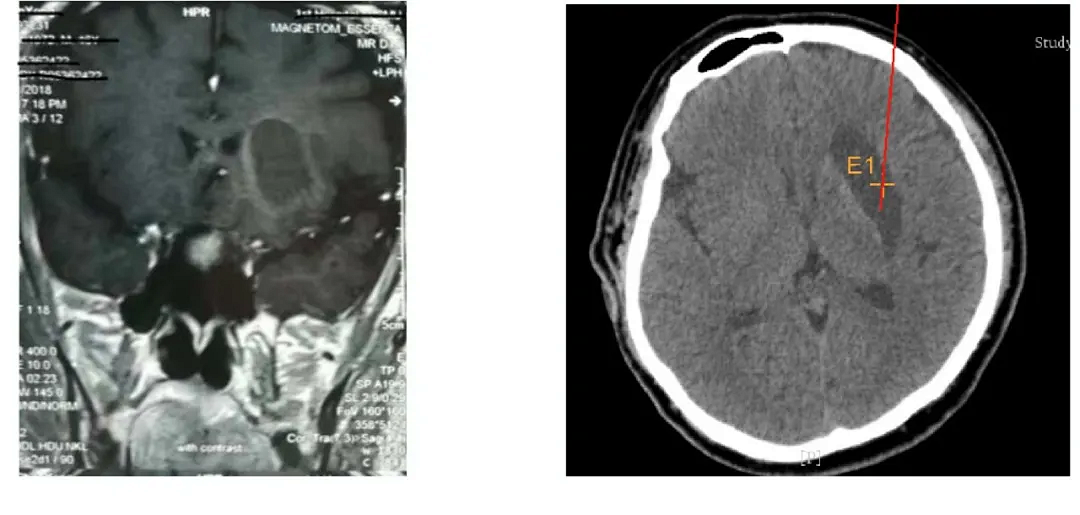

實施腦出血手術(shù)中

機(jī)器人輔助立體定向外科手術(shù)系統(tǒng)操作精度高,定位準(zhǔn)確,精度可達(dá)到0.5mm。如依靠機(jī)器人施行腦手術(shù),患者始終處于清醒狀態(tài)下,半小時左右手術(shù)即完成。術(shù)后3天,大部分患者就可走出醫(yī)院,實現(xiàn)了微創(chuàng)傷,縮短了患者術(shù)后恢復(fù)時間,手術(shù)成功率高。